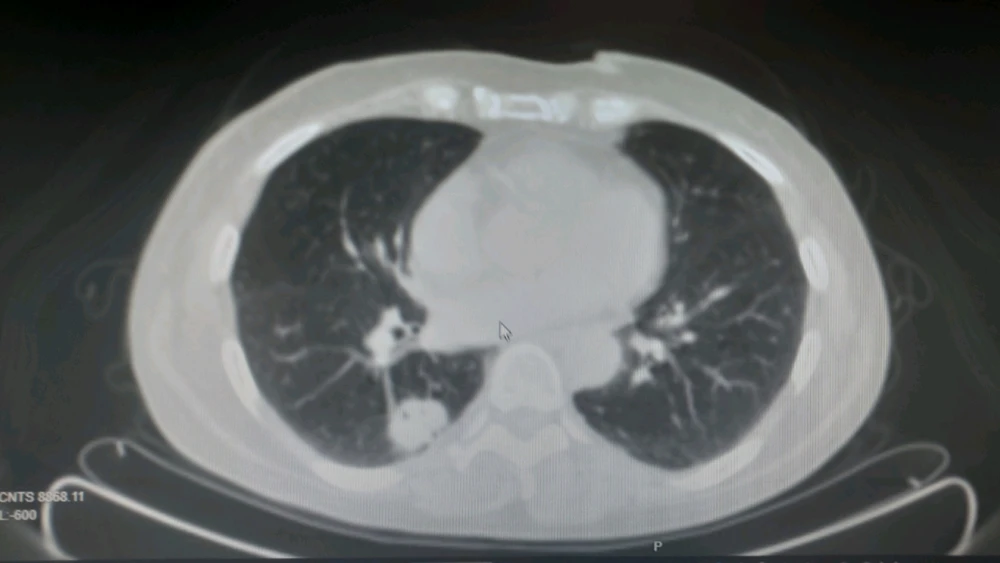

Nodulo pulmonar solitario en segmento superior de lóbulo inferior derecho (LID). A esto en radiología se le puede llamar de varias maneras, por ejemplo condensación pulmonar con bronquio abierto (el puntito negro que se ve en la imagen más blanca) en contacto con pleura (está pegada a pared... leer más